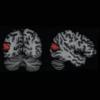

В исследовании приняли участие более ста здоровых взрослых людей; все они прошли психологические тесты, которые должны были выявить, насколько они вовлечены в социум или оторваны от него. Эти данные сравнивали с результатами сканирования мозга. Предполагалось увидеть, что одиночество будет сопровождаться какими-то особыми чертам в тех участках, которые сопряжены с тревогой, эмоциями, депрессией. Но всё оказалось иначе: самой чёткой была корреляция между степенью одиночества и количеством серого вещества в левой задней верхней височной борозде.

По словам учёных, эта зона отвечает за оценку базовых социальных сигналов; благодаря задней верхней височной борозде мы можем, например, по выражению лица понять, в каком настроении другой человек, интересен ли ему разговор или же он думает о чём-то постороннем и т. д. Если эта борозда плохо работает — а недостаток серого вещества не может не сказаться на ней, — то общаться с другими действительно может быть весьма непросто. Исследователи попробовали подтвердить свою догадку с помощью простого теста: испытуемым предлагали взглянуть на несколько фотографий и определить, в какую сторону смотрят люди на снимках. Как и ожидалось, те, у кого серого вещества в упомянутой борозде было меньше, затруднялись с заданием: им было сложно определить, влево или вправо глядит человек.